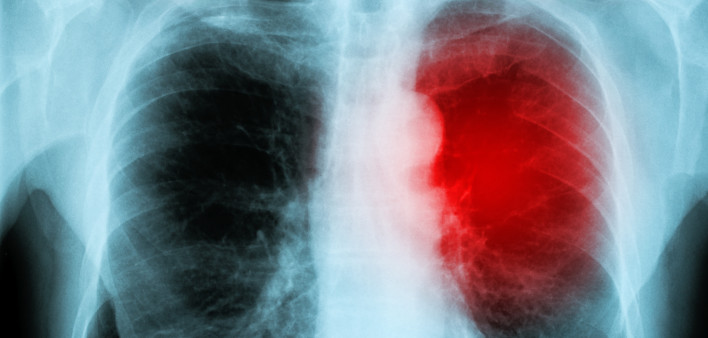

Diagnoses of the life-threatening bacterial infection of the heart valves known as infective endocarditis have increased over the past decade among people with hepatitis C virus (HCV), especially among young adults with the virus and those with opioid use disorder.